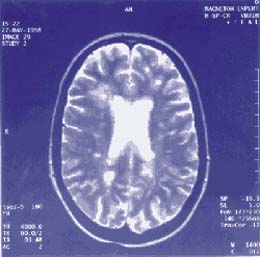

Ressonância nuclear magnética

Ressonância Magnética Nuclear

Lesões à vista?